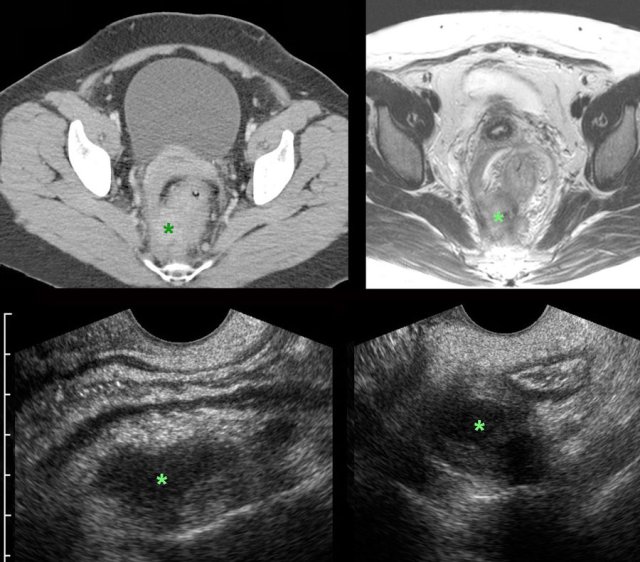

In this young lady with unexplained chronic abdominal symptoms for many years, CT and subsequent MRI demonstrated extensive endometriosis.

In addition there are large, adhesive endometriotic cysts (“kissing ovaries”),   bilateral hydronephrosis and complete obstruction of the colon, due to ingrowth of endometriosis in the ureters and the rectum.